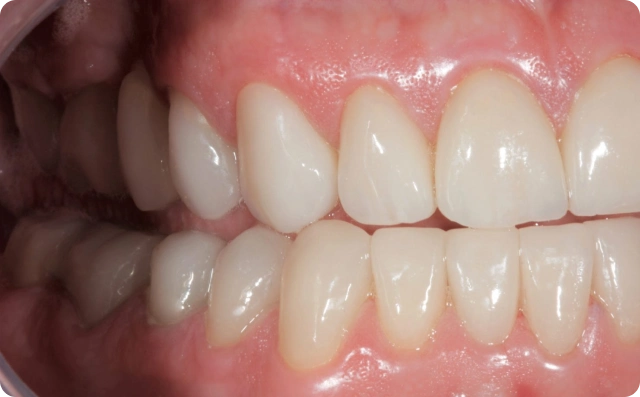

Depois

Foram confeccionadas facetas cerâmicas de dentes caninos a caninos superiores e inferiores, ponte fixa na região superior direita e coroas unitárias em dissilicato de lítio nos pré molares e molares.

Só após ter sido restabelecida a saúde bucal e ter alcançado a estabilidade oclusal é que foi finalizado o caso clínico.